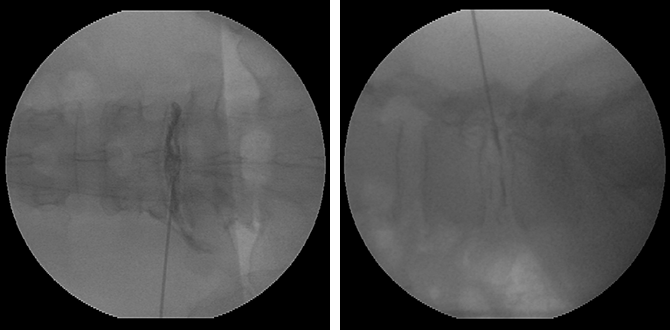

④ 추간판조영술

(Provocation Discography)

디스크성 요통, 퇴행성 디스크질환, 디스크탈출증 등 진단하는 검사입니다.